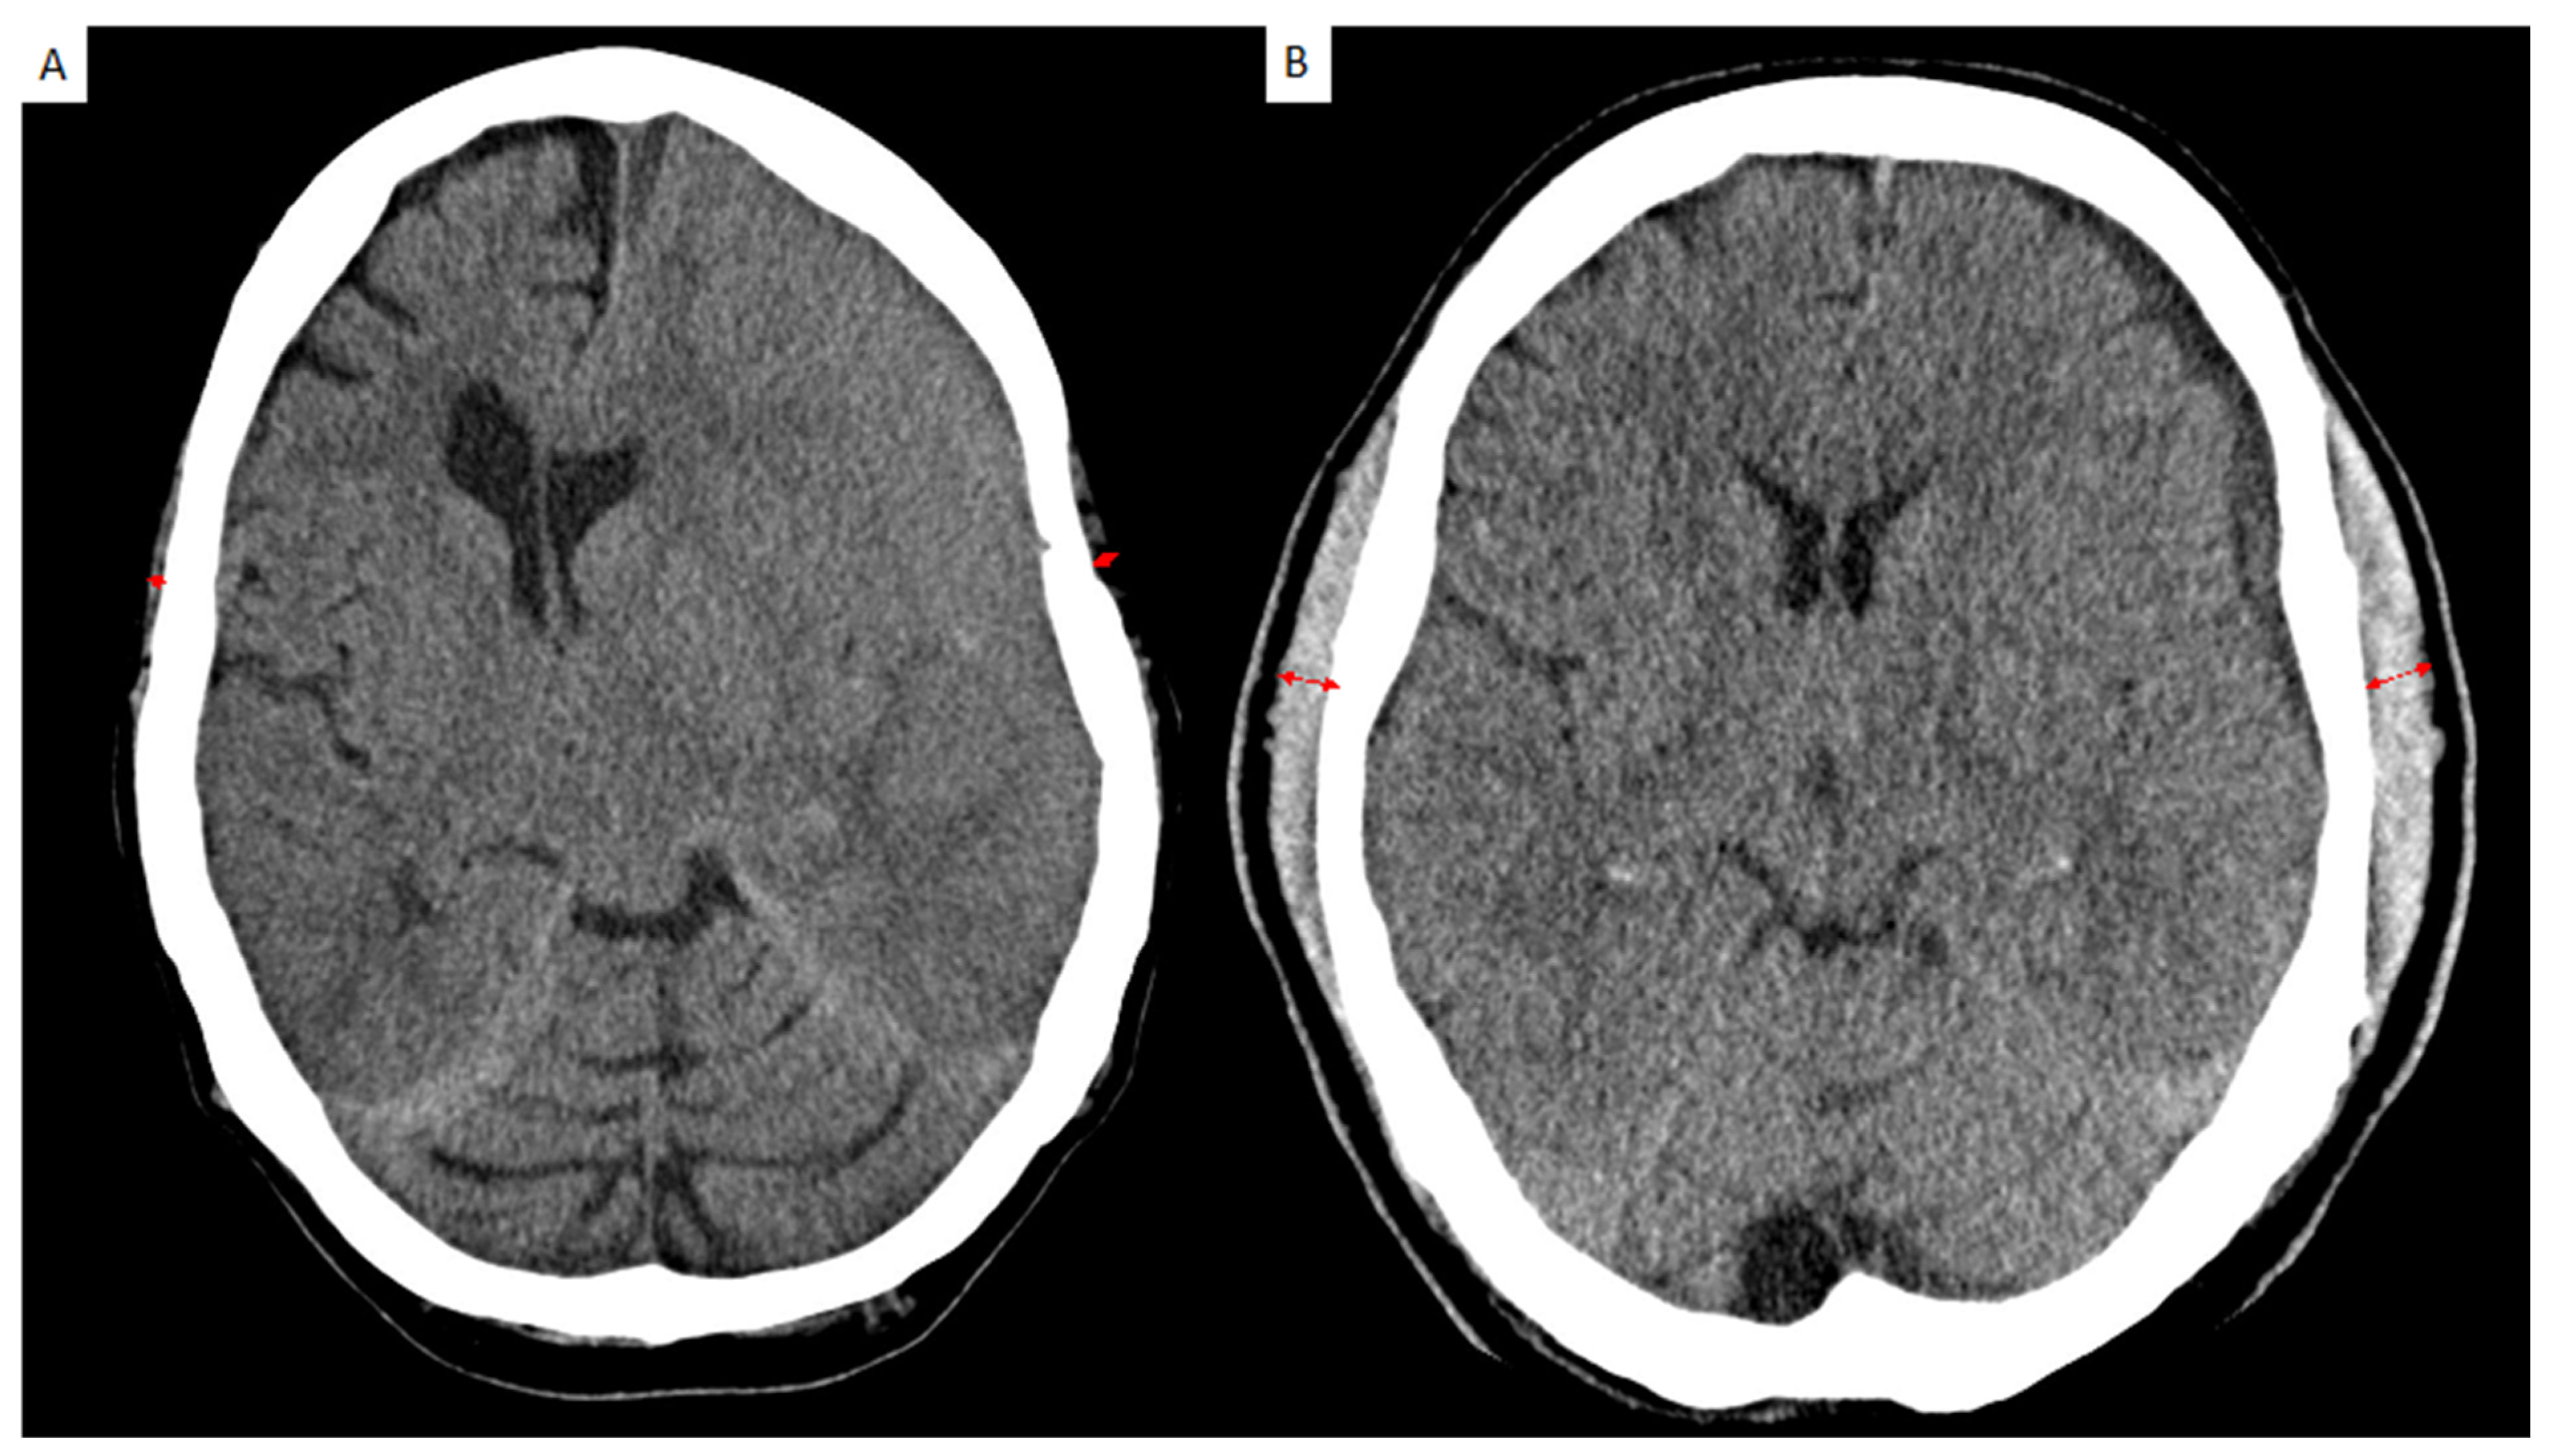

2.2. Image Analysis